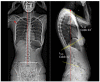

Upper cross syndrome (UCS) is a condition caused from prolonged poor posture manifesting as thoracic hyperkyphosis with forward head and shoulder postures. It has been associated with several other secondary conditions, causing pain and discomfort to those with the condition. This is a case report of a 35-year-old female presenting to clinic with a sharp pain in the neck, upper back, and sternum area for 4 weeks and gastroesophageal reflux disease (GERD). She had been working at home for several months after the shelter at home order was issued. Following evaluation and corrective treatment with cervical adjustment and soft tissue massage, the patient's posture improved and reported full pain resolution. Her symptoms of GERD concurrently resolved as well. She continued to receive chiropractic adjustment two times per month for correcting spinal misalignment. Full restoration of posture was attained on the full spine radiographs at 9 months follow-up. The patient remained symptom-free at 12 months follow-up. Manipulative and preventive therapies aimed at treating and preventing UCS should be more widely adopted to prevent secondary conditions.